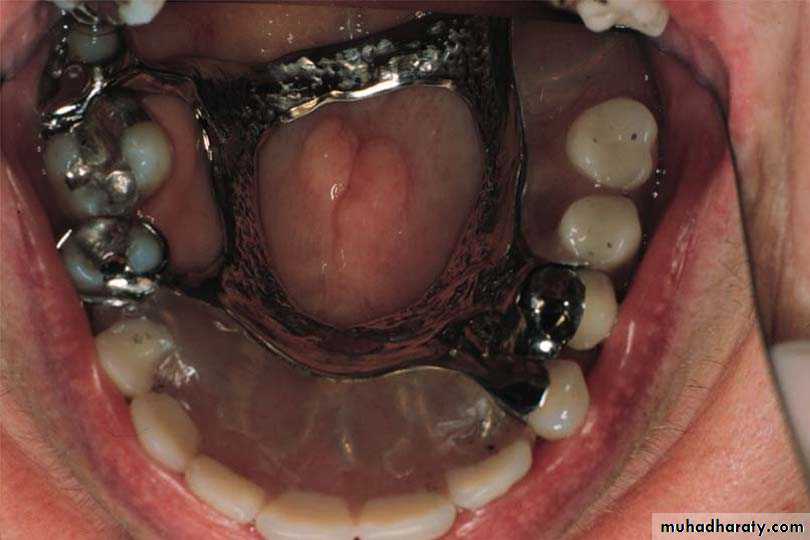

2-Single palatal bar

2-Single Palatal Bar(Can be used only in classIII) .

Design1-It is bar shape running across the palate

2-It has Narrow(half-oval cross section) anterio-posteriorly

Thick occluso-gingivally